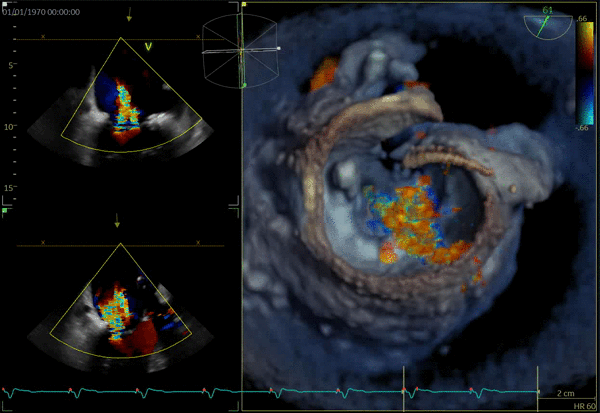

TMVR

- Cvi42 Mitral, distribuito da GE per Circle Cardiovascular, è un'applicazione leader che offre un set di strumenti e un flusso di lavoro completi per la valutazione della valvola mitrale. Accessibile solo su AW 4,7. Cvi mitral è venduto separatamente. Potrebbe non essere disponibile in tutti i mercati. Contattate il rappresentante commerciale locale

- 15596_MVQ_Whitepaper_v7.pdf